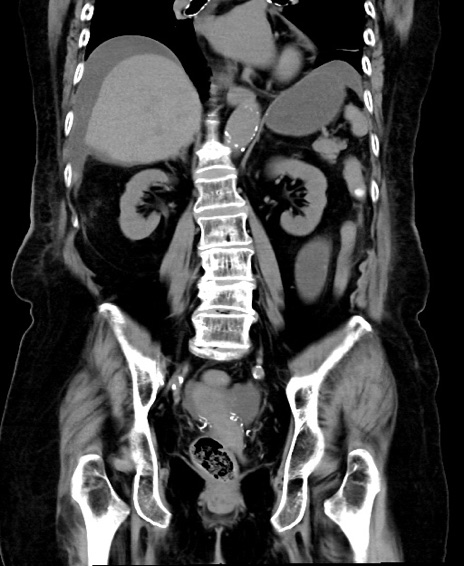

冠状断像

横断像